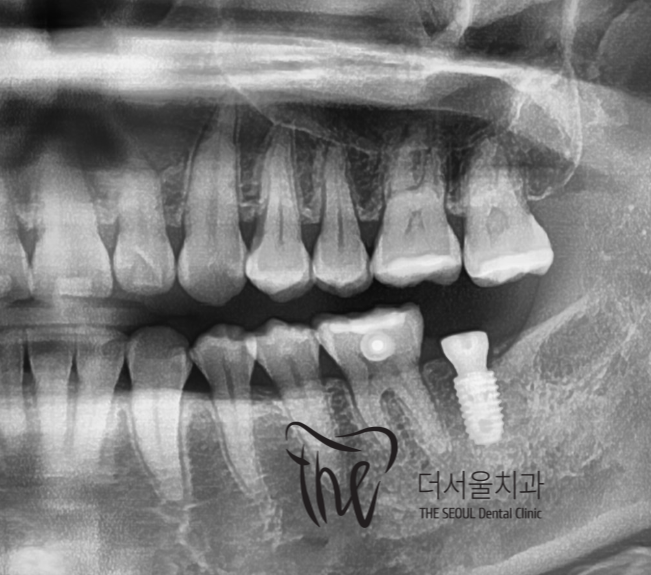

그러면서, 교정치료가 다 끝나가는 시점에서

임플란트를 심어서 맞물리는 대합치와의

기능 재건도 같이 진행했습니다.